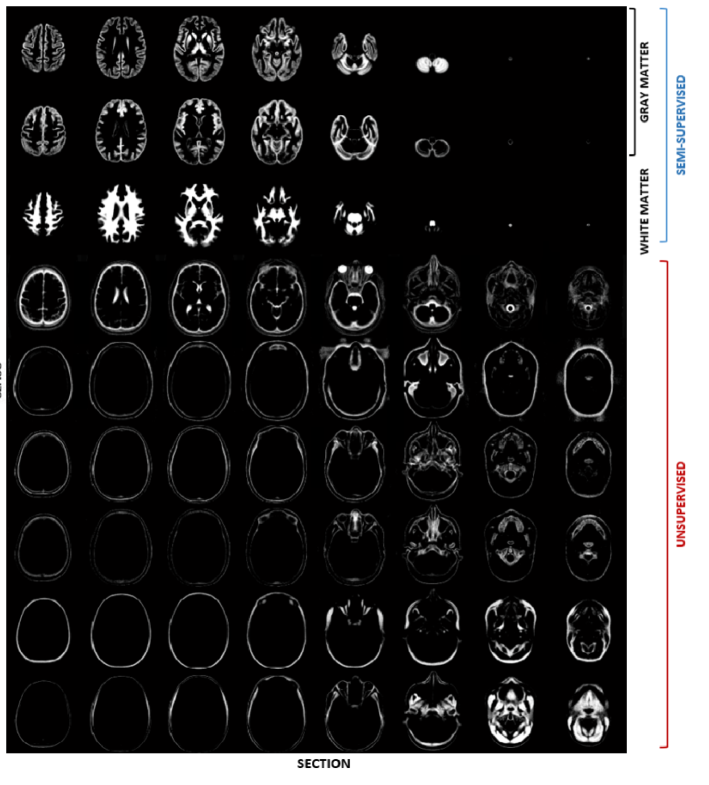

Analogously, in spite of having defined only one gray matter training label, two distinct gray matter classes were introduced in the mixture model (top two rows in Figure 2), to best capture the corresponding distribution of image intensities, which is poorly represented by a single Gaussian component, as opposed to the distribution of white matter intensities. Also in this case, membership probabilities of the labelled training data were computed based on the corresponding intensity values, by making use of equation (15).

The tissue probability maps obtained by applying the modelling framework presented in this paper to the data set described above are depicted in Figure 2. The total number of tissue classes used for this experiment is equal to twelve but three classes, representing air in the background, are not shown.

In particular, Figure 2 shows how one of the two gray matter classes (first row) best fits the subcortical nuclei and also includes voxels affected by partial volume effects at the interface between gray and white matter, while the second one (second row) is more representative of cortical structures, with the presence of partial volume effects generated by the juxtaposition of gray matter and CSF. The third row in Figure 2 shows the white matter class, which also includes most of the brainstem and the spinal cord.

The remaining tissue classes were estimated in a purely unsupervised way. Therefore a non ambiguous anatomical interpretation is not straightforward.

Fat and soft tissues are mainly represented in the last two classes (bottom two rows in Figure 2).

Refer to caption

(a)

Figure 2: Tissue probability maps obtained by applying the presented groupwise generative model to a multispectral data set comprising brain and cervical cord scans of eighty healthy adults, from three different databases.